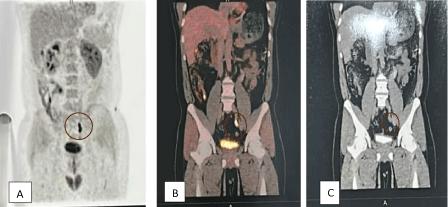

Ureteric Fibroepithelial Polyp in a Child-Recurrent Presentations and Diagnostic Dilemma Open Access

Ureteric Fibroepithelial Polyp in a Child-Recurrent Presentations and Diagnostic Dilemma

Swamy KB, Govani DR, Mehta AR, et al.

Benign ureteral polyps, also known as fibroepithelial polyps, can cause upper urinary tract obstruction by growing to block the flow of urine from the kidney. Fibroepithelial polyps are very rare benign lesions originating from the mesoderm. We have presented an interesting and unusual case who…...